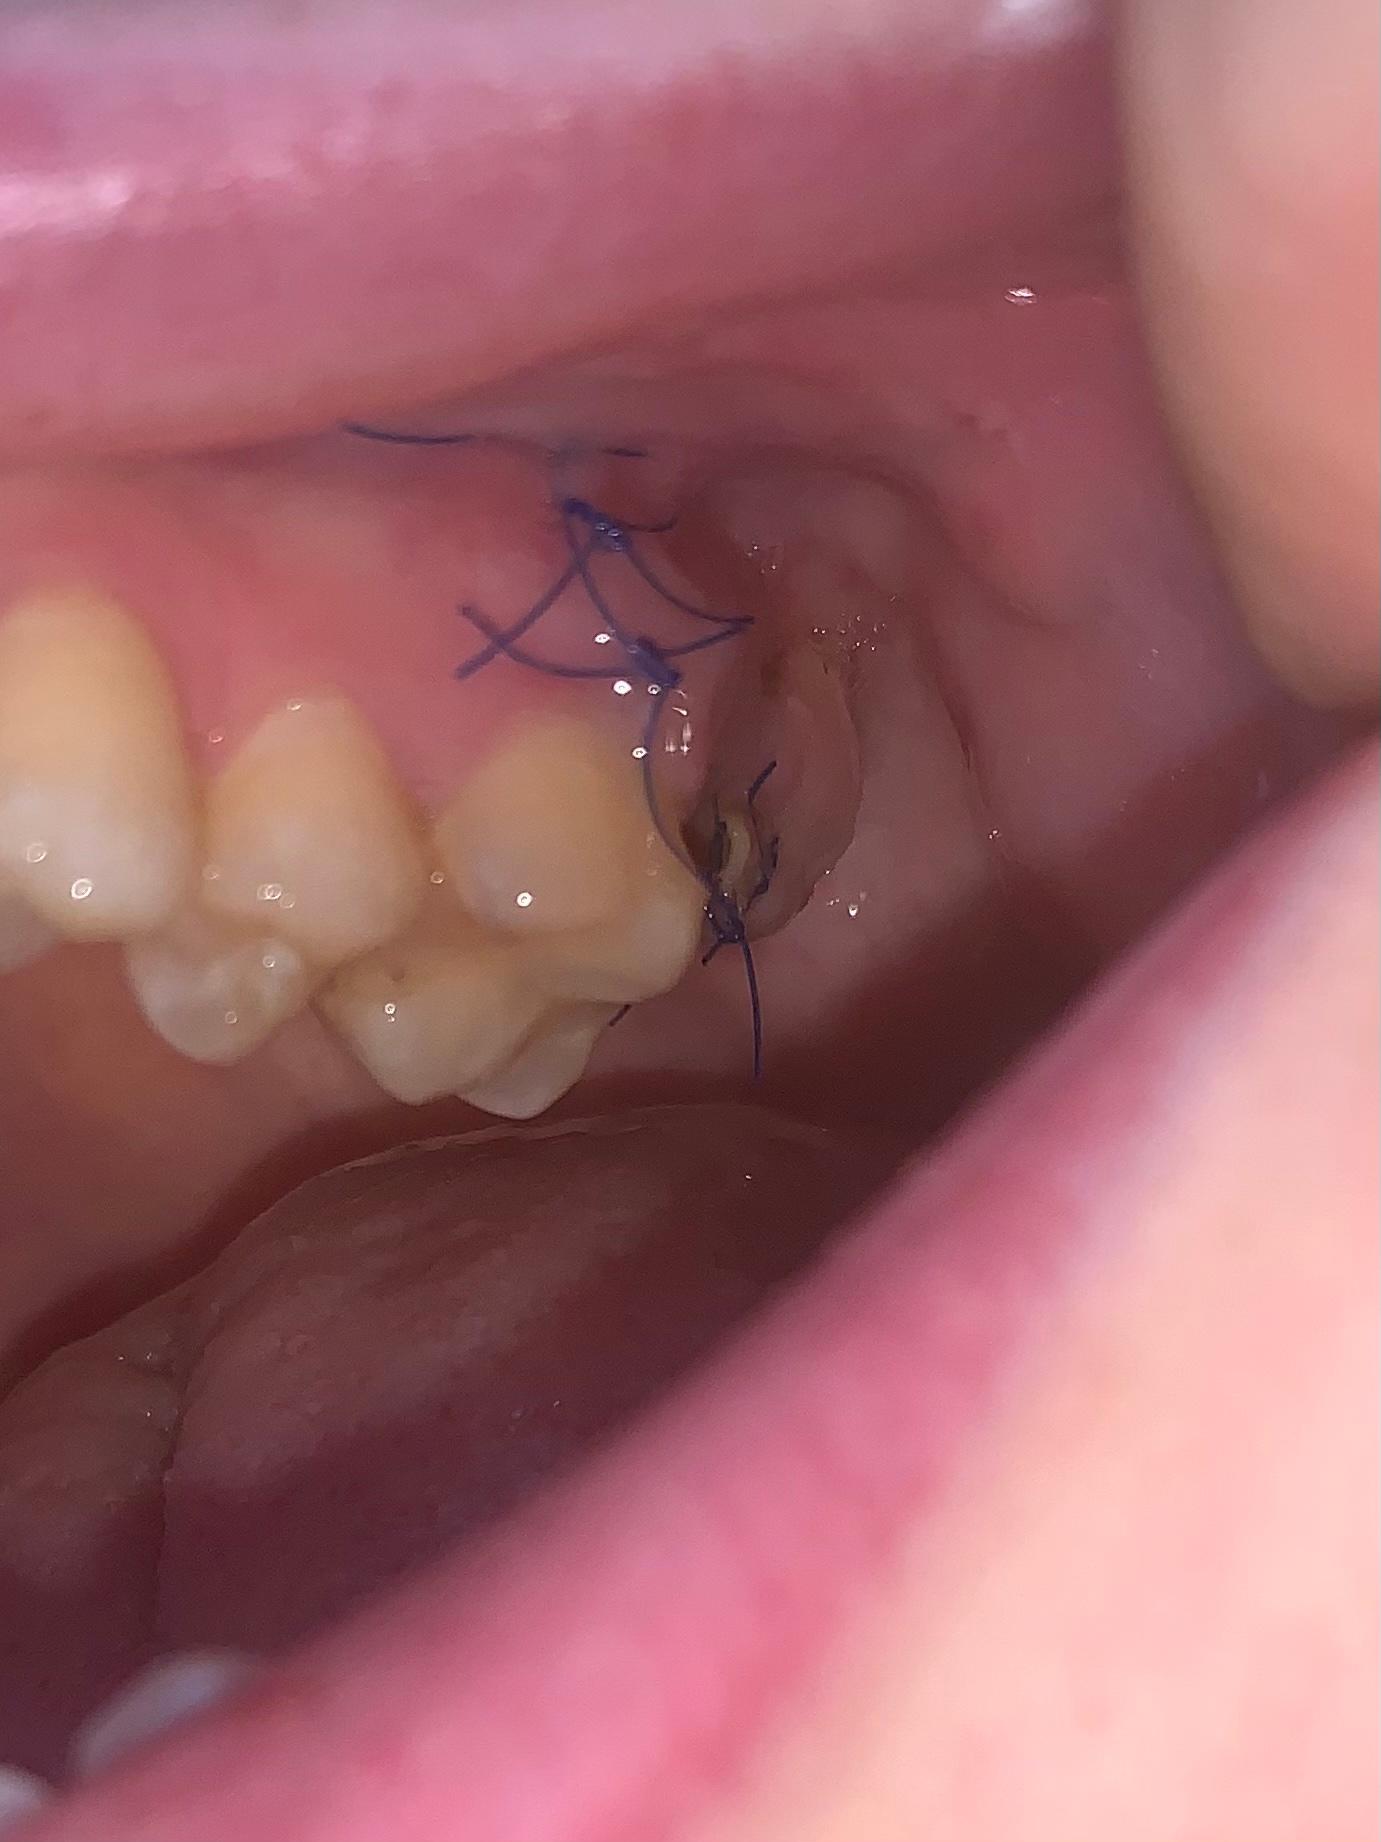

Dort entscheidet der Zahnarzt auch ob die Fäden gezogen werden können. Da eine Weisheitszahnwunde aufgrund der OP auch nach 3 Monaten noch nicht völlig verschlossen ist haben sich dort Speisereste festgesetzt wodurch Du jetzt eine Entzündung hast. Nach etwa zwei Wochen waren die Wunden komplett verheilt die Schwellung war weg und auch die Blutergüsse sind verschwunden.

Mir wurden vor etwas über drei Wochen alle vier Weisheitszähne operativ entfernt. Verhalten nach einer Weisheitszahn OP. Krater entstehen in denen sich uU.

Der erste Tage nach der Weisheitszahn OP. Nicht annähernd so stark wie nach der op aber dennoch sichtbar. Die Wunde wieder zu öffnen und die Wunde zu reinigen. Um den Mund sauber zu halten und Infektionen zu vermeinen können ab dem zweiten Tag die Zähne sanft geputzt werden. Bei den meisten Menschen zwischen 17 und 24 Jahren kommt es zum Wachstum von Weisheitszähnen. Bis sich die Wunde nach der Weisheitszahn OP geschlossen hat dauert es nur einige Tage. Jetzt habe ich von einigen gehört und im Netz gelesen dass nach dem entfernen der Fäden Löcher bzw. Das Kauen würde eine zu hohe Belastung für dich darstellen und die Wunde könnte aufgehen. Sie werden die Auswirkungen dann als minimal wahrnehmen und die Weisheitszahn-Operation als kleinen Eingriff.

Grundsätzlich ist die Einhaltung der Anweisungen und Verbote des behandelnden Arztes nach der Weisheitszahn OP entscheidend. Dies ist in den meisten Fällen so damit man sagen kann dass nach 7 Tagen bei der Mehrheit der Patienten die Heilung. Nach Weisheitszahn-OP Komplikationen nach Weisheitszahn-OP. Dort entscheidet der Zahnarzt auch ob die Fäden gezogen werden können. Daher sollten Sie während der ersten Zeit nur Brei und einfach zu kauende Lebensmittel zu sich nehmen. Daher sollte Obst bereits aus diesem Grund nicht als festes Lebensmittel gegessen werden. Um den Mund sauber zu halten und Infektionen zu vermeinen können ab dem zweiten Tag die Zähne sanft geputzt werden.